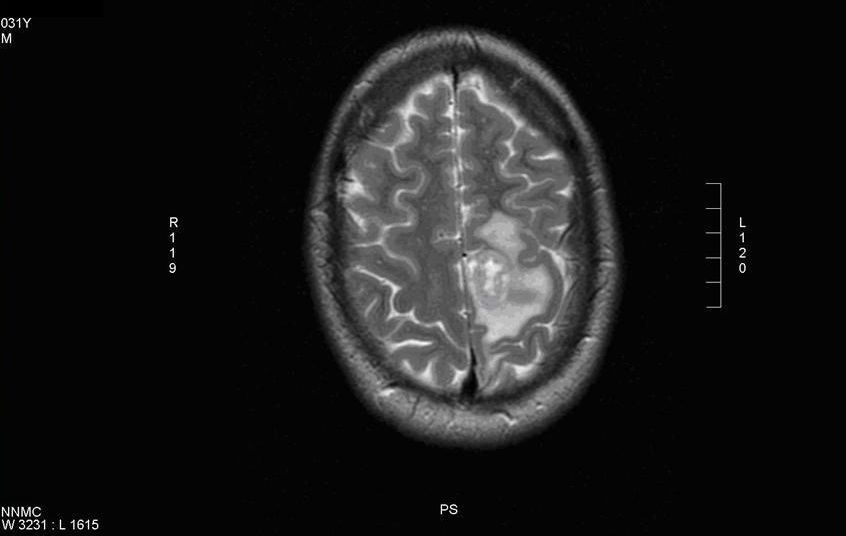

Ученые утверждают, что в итоге влияния носитель вируса становится неразумным. Как следствие, человек начинает плохо обрабатывать информацию, полученную извне, визуальная ...

Американские ученые утверждают, что частая раздражительность, гнев либо агрессия может быть вызвана особым видом микробов, паразитирующих на мозге человека. Оказалось, чт...